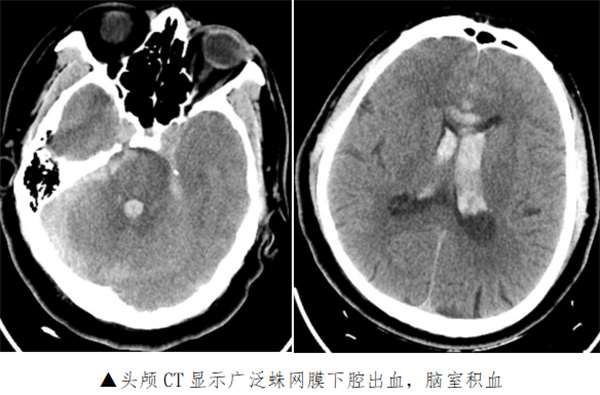

患者韩先生,入院3天前洗澡后出现头痛头晕,未诊治,因症状加重前来清华大学附属垂杨柳医院神经内科门诊就诊。期间,患者头痛剧烈,伴恶心呕吐,被紧急送至急诊科,头颅CT提示蛛网膜下腔出血、脑室出血(Fisher分级4级)。随即患者出现昏迷,GCS5分,呼吸困难,急诊行气管插管,呼吸机辅助呼吸,并联系医院神经外科前来急会诊。

手术于复合手术室进行。先用血管造影机行CT检查提示脑室出血增多,脑室铸型,急性脑积水形成。团队立即行左侧脑室钻孔引流术,于左侧脑室内放置脑室引流管,颅内压极高,引流血性脑脊液。随后行脑血管造影提示左侧大脑前动脉A2段动脉瘤,团队采取微创治疗,应用支架辅助,于动脉瘤内填入3枚弹簧圈,造影显示动脉瘤完全闭塞,载瘤动脉通畅。手术历时3小时,手术完毕后行CT检查未见新发颅内出血,脑室引流管位置良好。

术后患者转入ICU,接受机械通气、镇静镇痛、防治脑血管痉挛、脱水降颅压等治疗。复查头颅CT见颅内出血逐渐减少,无脑梗死及脑积水。术后一周拔除脑室引流管,行气管切开术。患者病情逐渐好转,术后3周脱离呼吸机,转至当地康复医院继续治疗。出院时患者能自动睁眼,左侧肢体可活动。